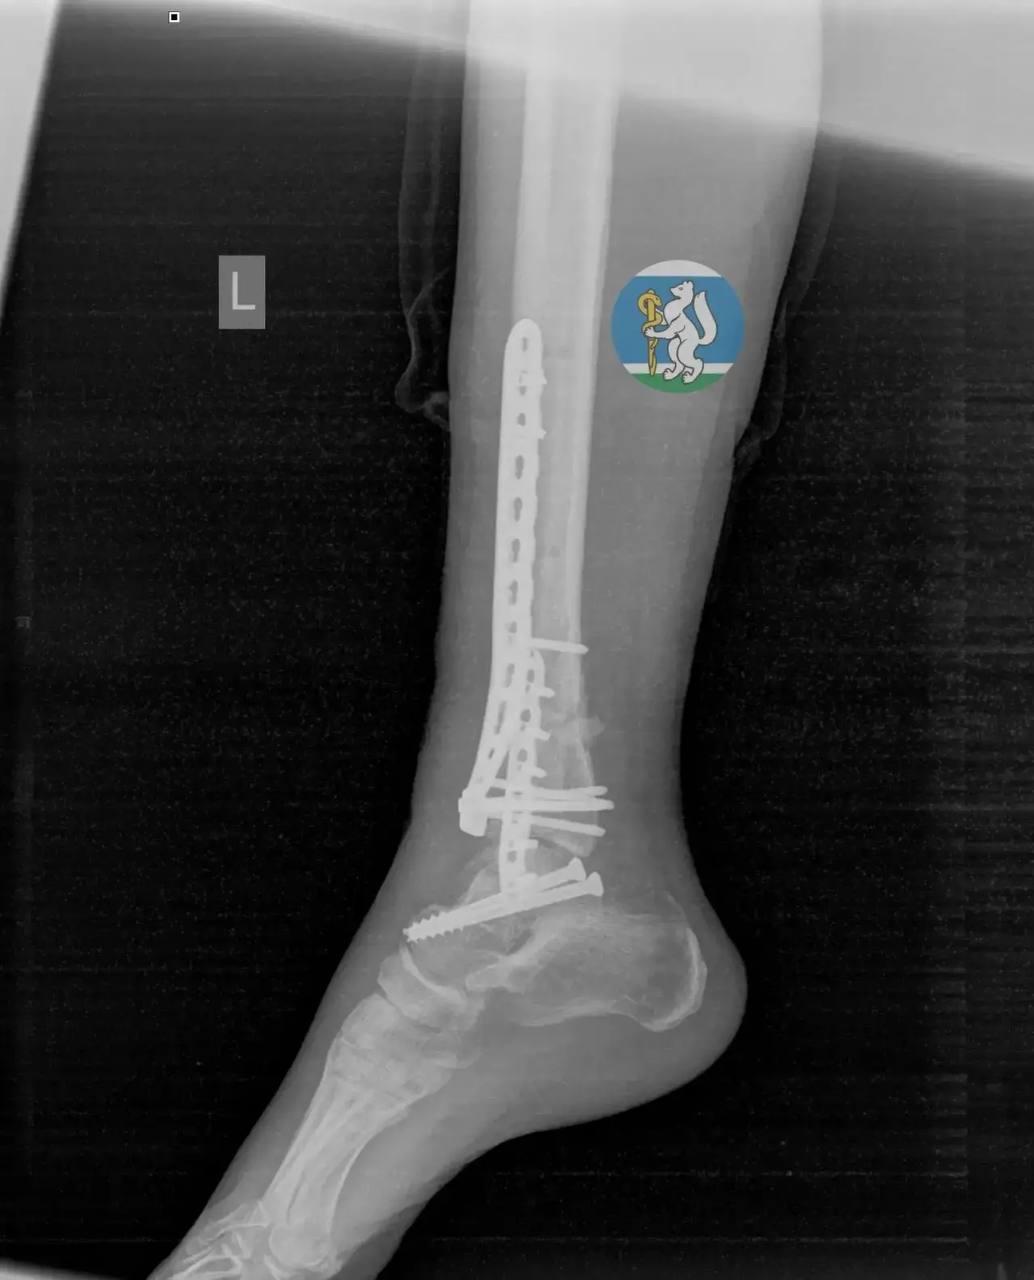

В городскую больницу №36 пострадавшую доставили в состоянии тяжелейшего травматического шока. Обследование выявило у нее черепно-мозговую травму, повреждение позвоночника, множественные переломы таза и открытые переломы ноги. Как отмечают врачи, большинство пациентов с такими повреждениями не доживают даже до прибытия в медучреждение.

После экстренной операции женщина находилась на искусственной вентиляции легких в реанимационном отделении. Через полторы недели её перевели в травматологию, а спустя ещё две недели медики успешно провели операцию по частичному демонтажу аппаратов внешней фиксации и синтезу сломанных костей.